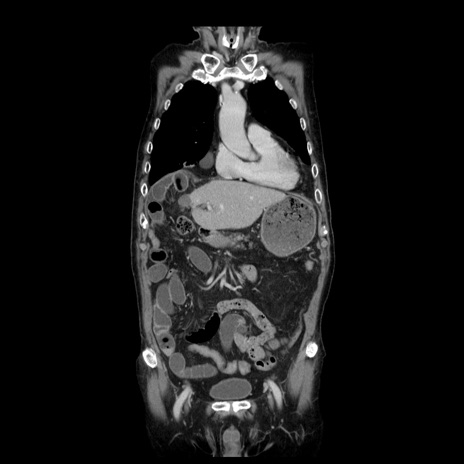

症例21(冠状断像)

【症例】70歳代男性

【主訴】腹痛

【現病歴】肝硬変・肝細胞癌にてかかりつけの方。約9時間前に食後より腹痛出現。症状が徐々に増悪し、嘔吐出現したため来院。

【既往歴】肝硬変、肝細胞癌(RFA、TACE後)

【身体所見】意識清明、表情苦悶様、BT 36℃、BP 129/78mmHg、P 88bpm、SpO2 97%(RA)、右上腹部から心窩部にかけて圧痛あり、反跳痛なし、筋性防御あり。

【データ】WBC 5800、CRP 0.16